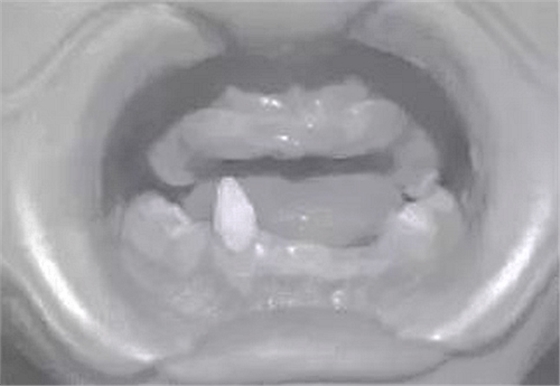

患兒,男,8歲,因“先天缺牙2年.要求鑲牙”于2010年7月就診于我科?;純杭议L訴孩子牙齒先天發(fā)育不良,無法咀嚼,擔心孩子發(fā)育。檢查示:患兒智力正常,頭發(fā)及眉毛稀少,雙側(cè)面部對稱,囟門發(fā)育不足,腳趾并攏不全,口內(nèi)查11、12、13、14、15、21、22、23、24、25、31、32、33、34、35、41、42、44、45缺失,75、85為乳牙,43為錐形牙。牙槽嵴較低平,上下牙槽嵴未觸及明顯的骨突及骨尖,無咬合關系,頜間距短。雙側(cè)顳下頜關節(jié)區(qū)無壓痛、無關節(jié)彈響。

圖2患者修復前口內(nèi)像